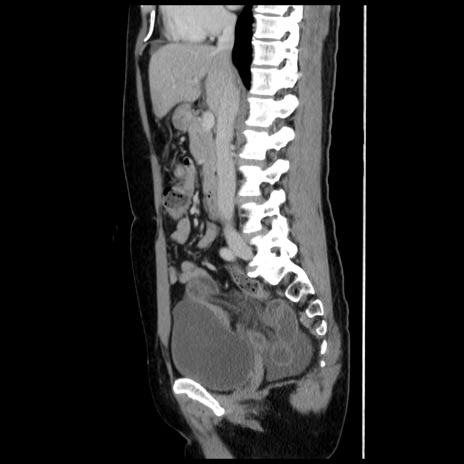

症例10(矢状断像)

【症例】 50歳代女性

【主訴】 腹痛

【現病歴】前日生レバーを食べた。今朝に排便あり。 昼前に突然発症の腹痛を生じ、当院救急外来を受診した。

【既往歴】 子宮筋腫にてで子宮全摘後

【身体所見】 意識清明、腹部:平坦、軟、下腹部やや左を中心に圧痛・反跳痛あり、筋性防御あり

【データ】WBC 7800、CRP 0.07